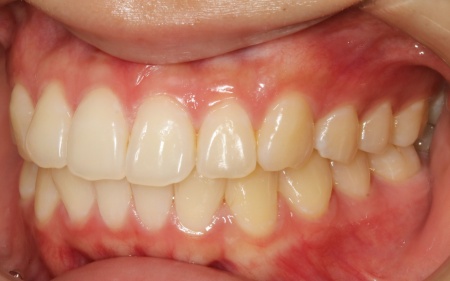

治療後